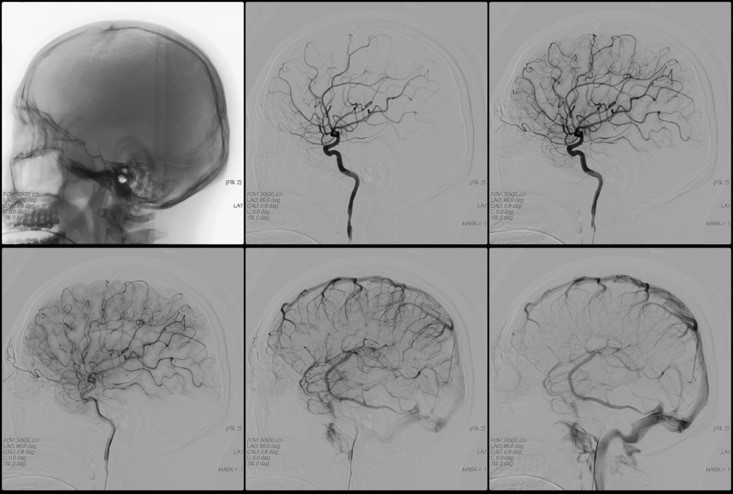

Ангиография магистральных артерий головы – это инструментальный метод исследования, позволяющий в буквальном смысле слова «увидеть» сосуды головного мозга. Для проведения исследования необходимо введение в соответствующий сосуд головного мозга контрастного вещества и наличие рентгеновского аппарата, с помощью которого будет зафиксировано изображение сосудов, заполненных этим контрастом. Ангиография сосудов головного мозга – это не рутинный метод диагностики, у него имеются свои показания и противопоказания, а также, к сожалению, и осложнения. Ангиография в широком смысле – это получение изображения любых сосудов организма с помощью рентгеновских лучей. Ангиография сосудов головного мозга – это лишь одна из разновидностей этого обширного метода исследования.

Суть этого метода исследования заключается в следующем. Больному в определенную артерию головного мозга (или всю сеть артерий мозга) вводится рентгенконтрастное вещество, обычно на основе йода (Оптирей, Омнипак, Ультравист и другие). Это делается для того, чтобы можно было с помощью рентгеновского излучения зафиксировать изображение сосуда, поскольку при обычном снимке сосуды плохо визуализируются. Введение рентгенконтрастного вещества возможно путем пункции соответствующей артерии через катетер, подведенный к необходимому сосуду с периферии (обычно из бедренной артерии). Когда контрастное вещество оказывается в сосудистом русле, производится серия рентгеновских снимков в двух проекциях Полученные снимки оцениваются врачом и делаются выводы о наличии либо отсутствии определенной патологии сосудов головного мозга.

Пациент укладывается на стол и подключается к приборам (кардиомонитор, пульсоксиметр). После обработки кожи местным анестетиком и обезболивания производится прокол соответствующего сосуда. Осуществляется небольшой разрез кожи и прокол бедренной артерии с последующим погружением катетера и проведением его по сосудам к месту исследования. Продвижение катетера по артериальному руслу не сопровождается болью, поскольку внутренняя стенка сосудов лишена болевых рецепторов. Контроль продвижения катетера производят с помощью рентгена. Когда катетер будет подведен к устью необходимого сосуда, через него вводится предварительно подогретый до температуры тела контрастный препарат в объеме 8-10 мл. Введение контраста может сопровождаться появлением металлического привкуса во рту, чувством жара, прилива крови к лицу. Эти ощущения самостоятельно проходят в течение нескольких минут. После введения контраста производятся рентгеновские снимки в нескольких проекциях почти каждую секунду несколько раз (что позволяет увидеть и артерии, и капиллярную фазу, и вены). Затем катетер удаляют, на место пункции сосуда накладывают давящую стерильную повязку. За пациентом должен наблюдать медицинский персонал как минимум в течение 6-10 часов.